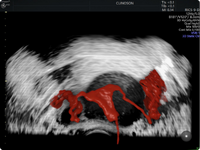

HyCoSy - Histerossonografia com Contraste

HyCoSy é um exame moderno, não invasivo e indolor, que substituiu a histerossalpingografia tradicional para avaliação das trompas e do útero. É ideal para mulheres que desejam investigar causas de infertilidade ou dores pélvicas com conforto e alta precisão diagnóstica.